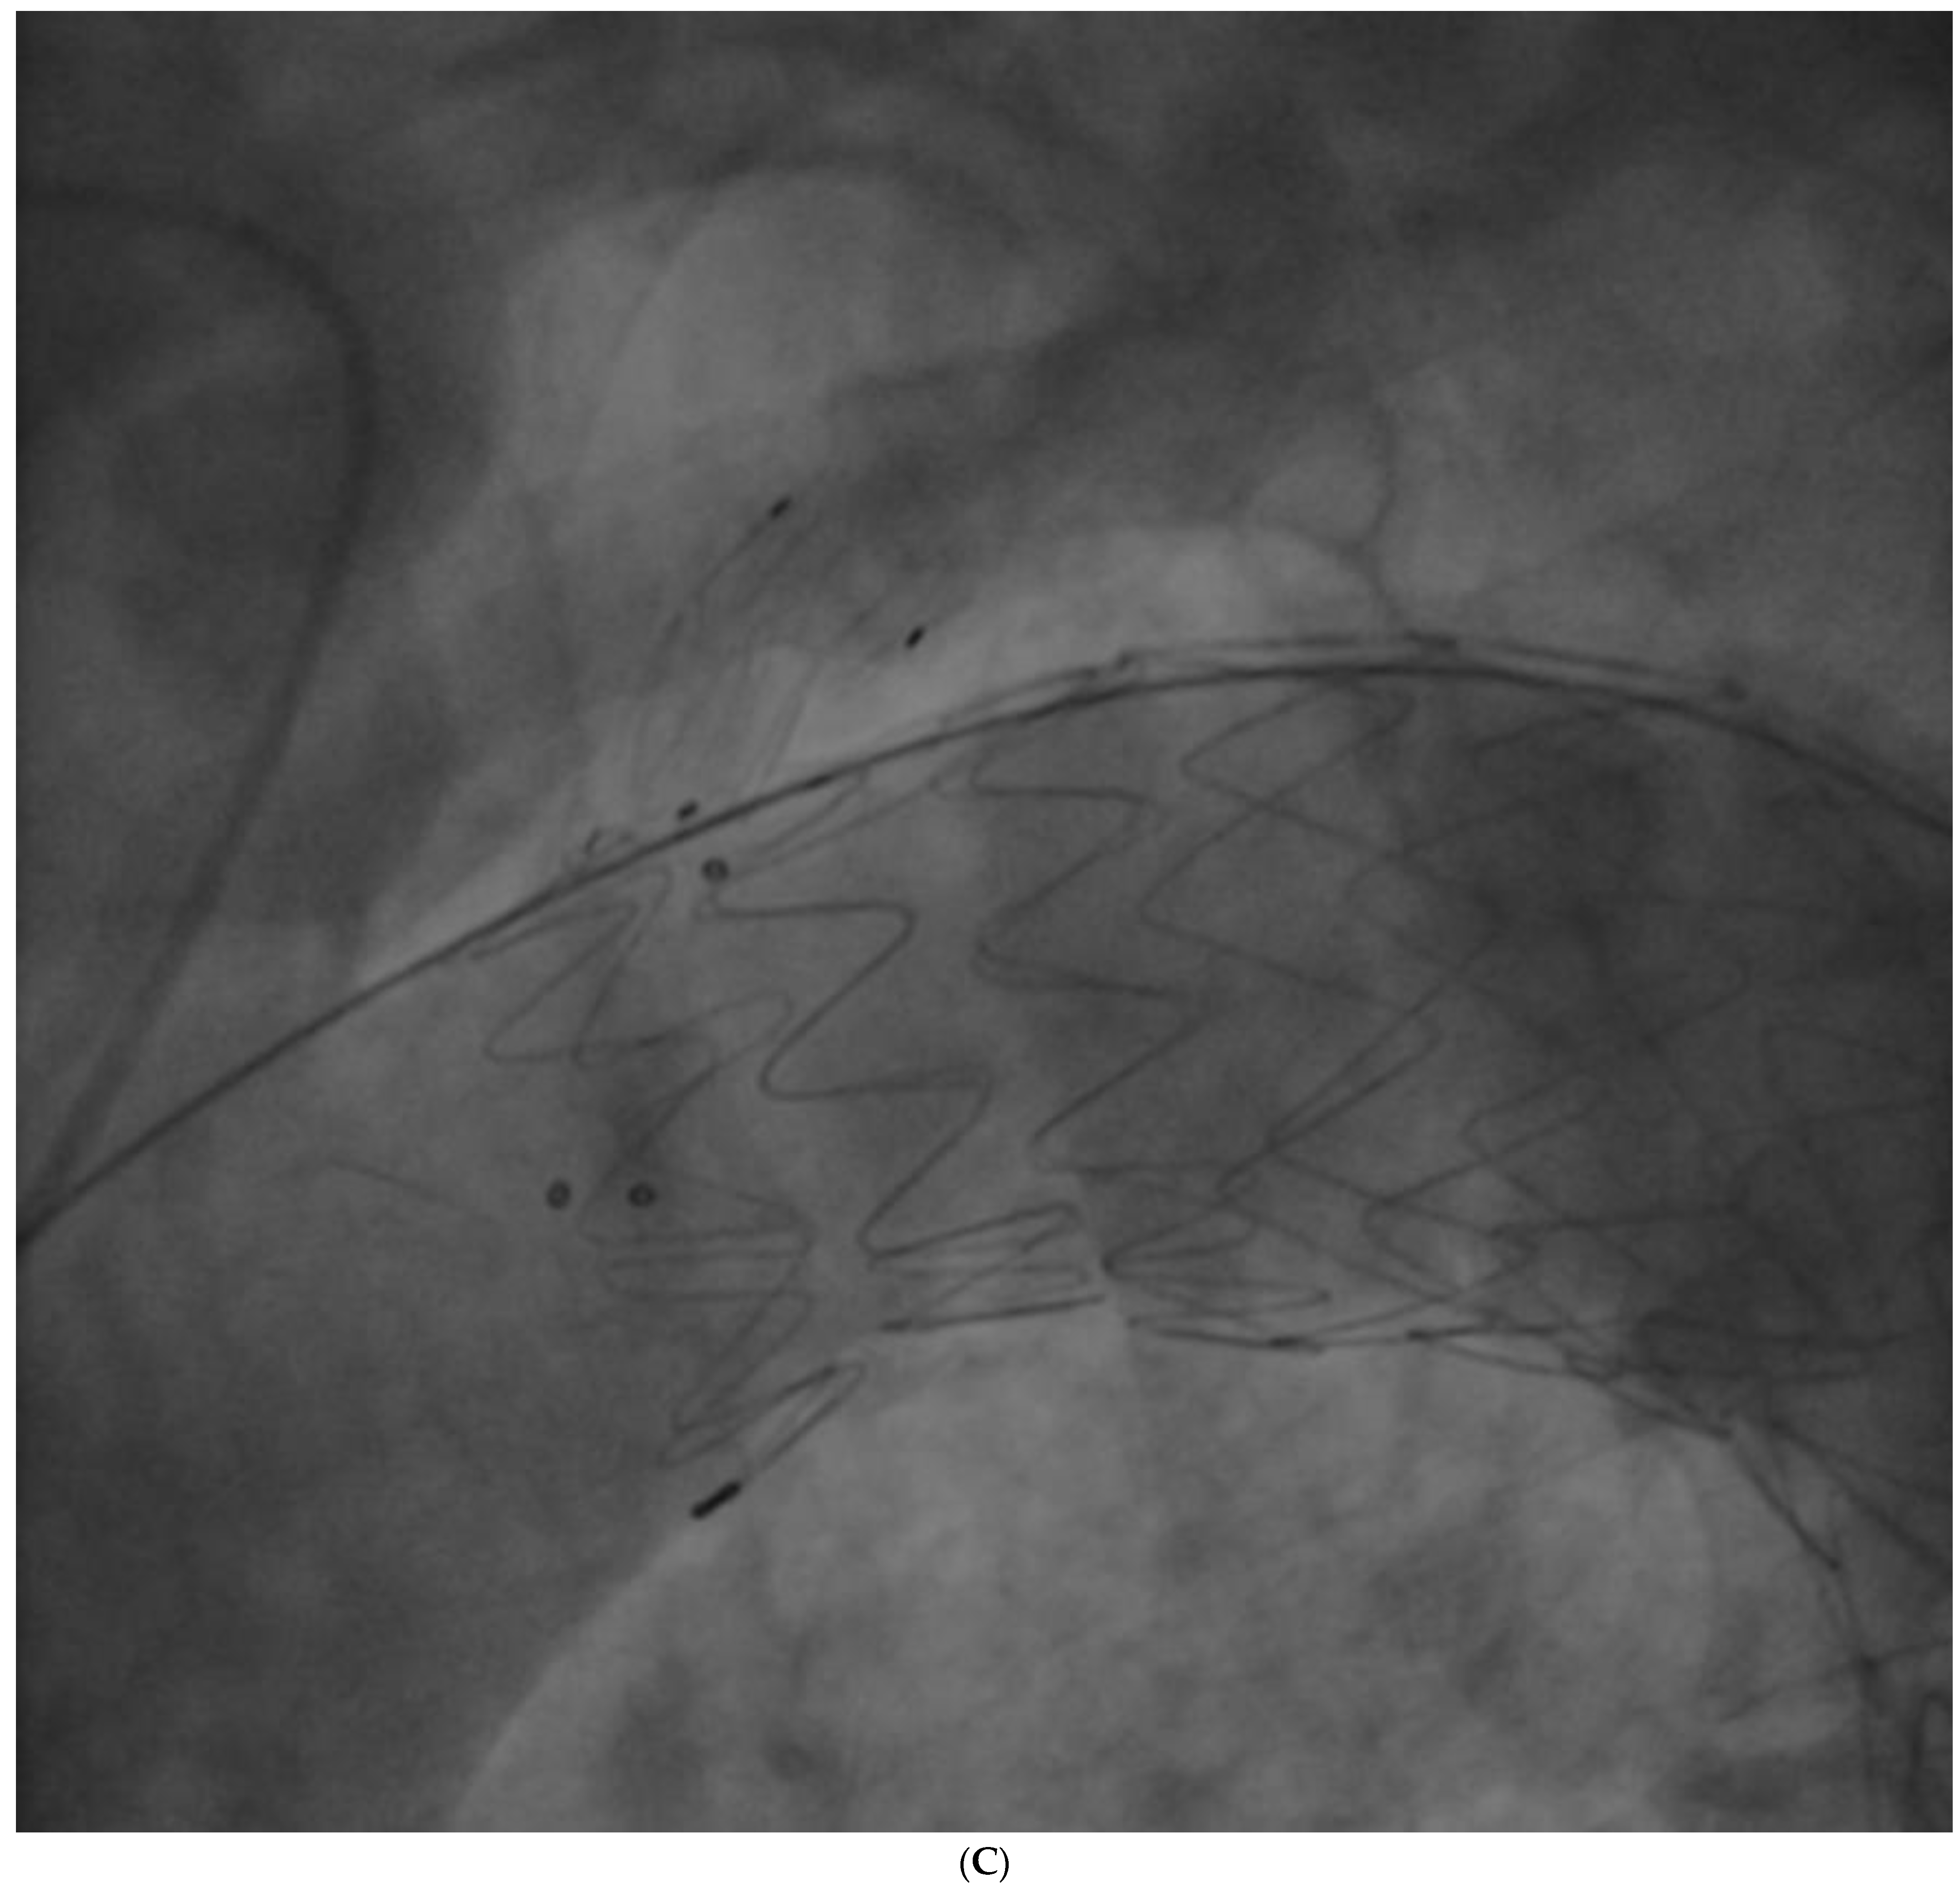

The procedure was performed in deep sedation. A 6 F pigtail was advanced through a right radial arterial access into the ascending aorta for aortic angiographies; then a 10 F right femoral arterial access was obtained with the pre-implantation of two percutaneous closure systems, and subsequently. upgraded to 18 F. Afterwards, an 8 F left brachial arterial access was obtained; a guidewire was advanced through the brachial access into the femoral access, forming a brachial–femoral loop; a dedicated catheter was advanced on the guidewire; then, an extra stiff guidewire (0.035″) was advanced through femoral access to ascending aorta, and the branch guidewire was positioned in the catheter introduced from the brachial access. A Castor 38 mm × 32 mm × 200 mm stent graft with a 12 mm × 25 mm branch for LSA was positioned and released at PAU level. The final angiography showed the exclusion of PAU, but also a small type 1 endoleak (Figure 5A) treated successfully with some balloon dilatations in the proximal graft lumen (Reliant Balloon, Figure 5B,C). This finding is likely due to graft malapposition caused by an enlarged ascending aorta and aortic arch. There were no complications during the procedure. The patient was discharged with anti-hypertensive treatment (candesartan 16 mg, hydrochlorothiazide 12.5 mg, amlodipine 5 mg), aspirin, plus clopidogrel (for 3 months, followed by low-dose aspirin only).

Figure 5. (A)—Type I endoleak observed after graft deployment; black arrows show endoleak. (B)—Balloon inflation for type I endoleak treatment. (C)—Final result after balloon inflation; no endoleak is observed.